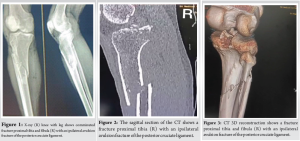

A 34-year-old male was admitted to the emergency department at S N Medical College, Agra, as a case of comminuted fracture proximal tibia and fibula (R) with ipsilateral avulsion fracture of PCL (Fig. 1-4), due to motorcycle-motorcycle collision 3 days before the admission.

We planned to manage both fractures in a two-stage surgery. The selected approach involved open reduction internal fixation of fracture proximal tibia by LCP followed by open reduction and internal fixation of PCL avulsion using cannulated cancellous screws, supplemented by the innovative application of a spiked washer for enhanced stability. Post-operative X-ray after open reduction and internal fixation of the proximal tibial fracture with an LCP (R) (Fig. 5). The implant is appropriately aligned, with satisfactory reduction and fixation of the fracture fragments, ensuring stability for healing. The interval between the two surgeries was 10 days, allowing time for the skin incision to heal and the soft-tissue swelling to subside. Following the acquisition of informed consent, the patient was planned for ORIF using cannulated cancellous screws and spiked washer, employing the modified posterior approach as detailed by Burks and Schaffer [6]. The patient underwent surgery under spinal anesthesia. He was placed in a prone position on a radiolucent operating table, ensuring adequate padding for pressure points. The lower extremity was positioned with a 30° flexion at the knee joint, supported by a bolster at the ankle, and a pneumatic tourniquet was applied to the patient. An inverted “L”-shaped incision was performed, starting from the medial aspect of the gastrocnemius and curving along the joint’s flexor crease toward the lateral side (Fig. 6).